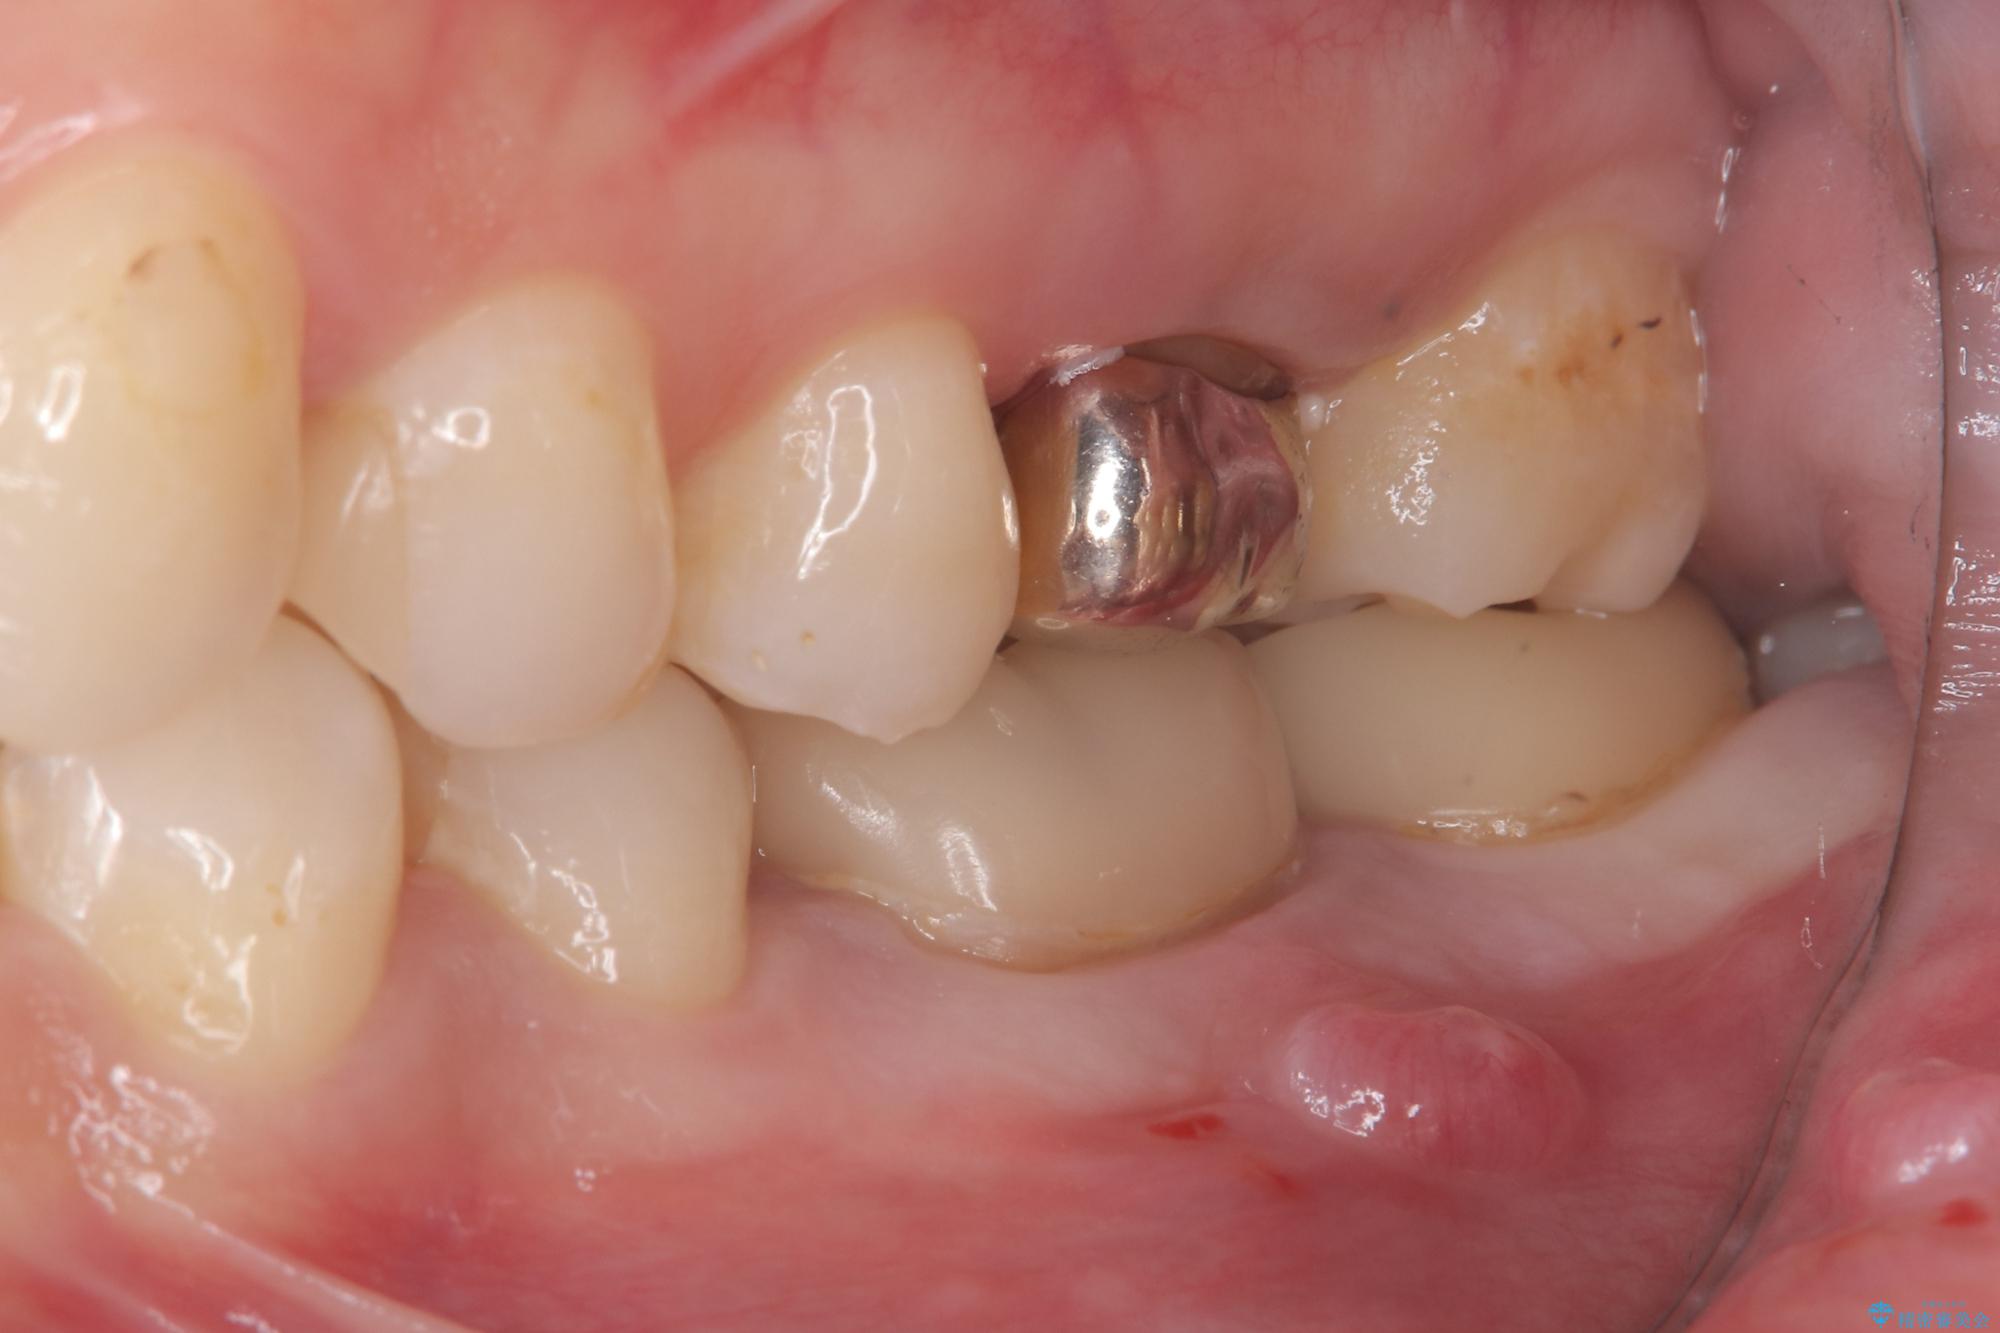

保存が難しい左下6番目の歯を抜歯し、左下8番目の歯(親知らず)を抜歯窩に移植しました。歯牙移植後の動揺防止のため暫間固定を行っています。

また移植後2週間経過時点で根管処置が必要となります。